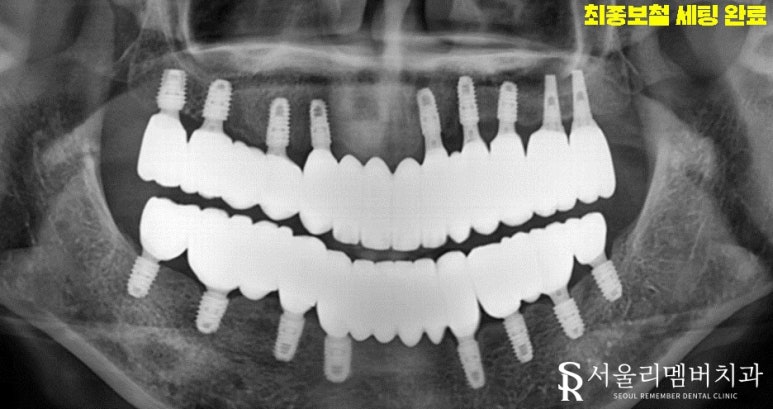

드디어 이수역 치과 의 전체임플란트 식립 이 끝이 났는데요.

위에 올릴 보철은 지르코니아를 사용하기로 했습니다.

아무리 보철이라도 자연치처럼 예쁘게 보이는 것이 중요하겠죠?

비교할 수 있는 인접치가 없더라도 안모, 분위기, 입술 등을 고려하여

위화감이 느껴지지 않도록 제작을 했습니다.

하얗고 고른 이가 무조건 예쁘다고 느껴질 수 있겠지만

개인의 얼굴형, 성별, 인종에 따라 치아의 형태는 제각각 달라지게 됩니다.

즉, 딱 자신에게 어울리는 모양이 있다는 거죠.

최대한 자연스럽게 제작하는 것이 보철을 오래 사용할 수 있는 방법이죠.

최종적으로 보철을 올려드린 후 이수역 치과 의 전체임플란트 과정이 마무리되었습니다.

이전보다 밝고 건강한 미소를 갖게 되었네요.

또한 울긋불긋 튀어나와있었던 잇몸 염증 또한 가라앉은 모습입니다.